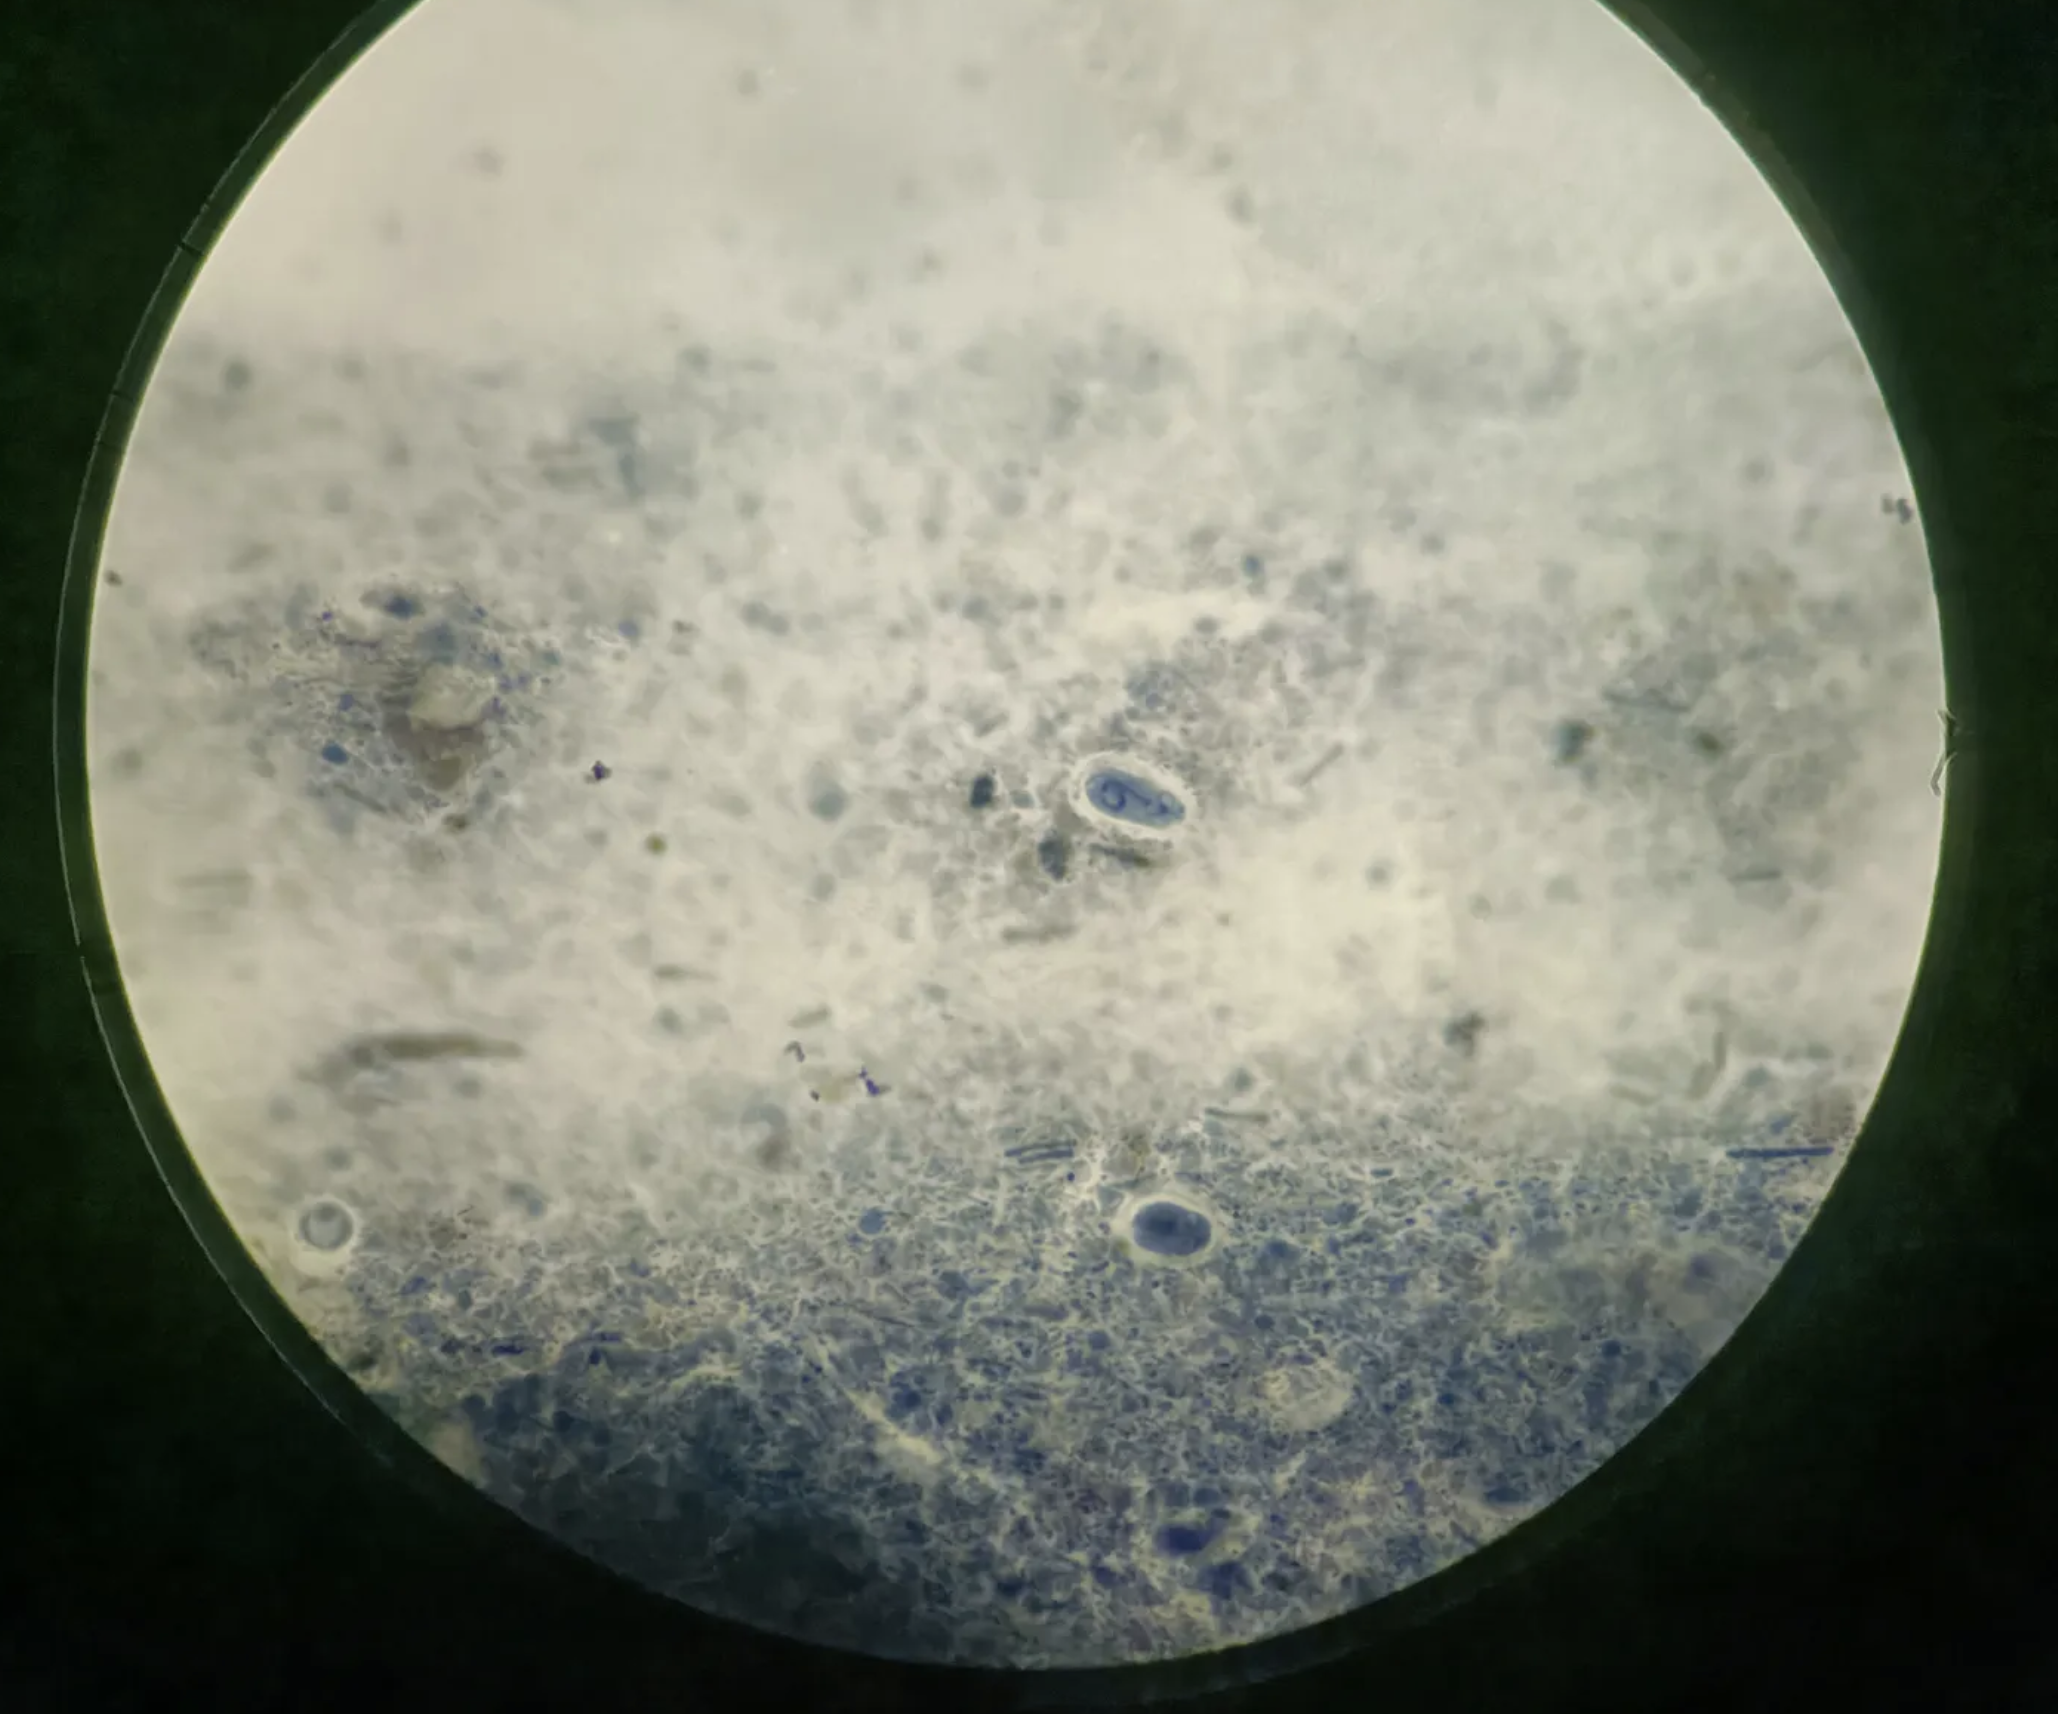

疟原虫

三期六种形态

1.滋养体期:小、大滋养体

2.裂殖体期:未成熟、成熟裂殖体

3.配子体期:雌、雄配子体

环状体

胞浆:环状,蓝色。

核:红色,

1个

大小约为红细胞直径的1/3

“红红的核,蓝蓝的浆”

间日疟大滋养体

虫体增大。

胞浆:不规则,蓝色,出现伪足,有空泡。

有烟丝状疟色素,黄褐色。

核:红色,一个。

感染红细胞胀大,出现薛氏小点。

间日疟未成熟裂殖体

虫体变圆,空泡消失。

红细胞胀大,褪色,有薛氏小点。

胞浆:蓝色,变多且尚未分裂。

核:开始分裂,2-12个。

疟色素烟丝状,集中成团。

间日疟成熟裂殖体

红细胞胀大褪色

裂殖子12-24个,平均16个。

疟色素黄褐色,常集于一边。